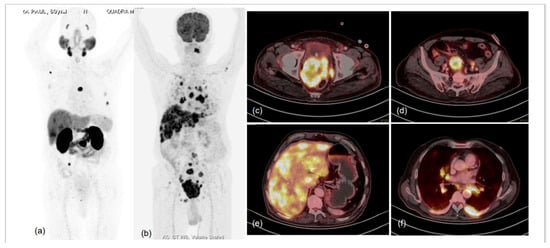

- Adnan, A.; Basu, S. Dual-Tracer PET-Computed Tomography Imaging for Precision Radio-Molecular Theranostics of Prostate Cancer: A Futuristic Perspective. PET Clin. 2022, 17, 641–652. [Google Scholar] [CrossRef]

- Adnan, A.; Basu, S. Concept proposal for a six-tier integrated dual tracer PET-CT (68Ga-PSMA and FDG) image scoring system (‘Pro-PET’ score) and examining its potential implications in metastatic castration-resistant prostate carcinoma theranostics and prognosis. Nucl. Med. Commun. 2021, 42, 566–574. [Google Scholar] [CrossRef]

- Alberts, I.; Schepers, R.; Zeimpekis, K.; Sari, H.; Rominger, A.; Afshar-Oromieh, A. Combined [68 Ga]Ga-PSMA-11 and low-dose 2-[18F]FDG PET/CT using a long-axial field of view scanner for patients referred for [177Lu]-PSMA-radioligand therapy. Eur. J. Nucl. Med. Mol. Imaging 2022, 1–6. [Google Scholar] [CrossRef]